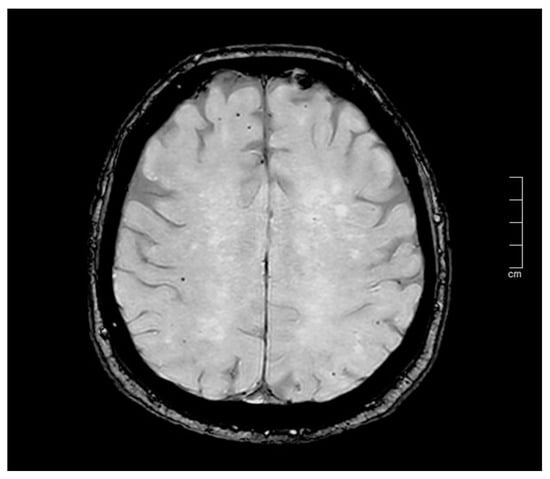

The accurate identification and quantification of CMBs vary significantly depending on magnetic field strength and the imaging technique used, such as SWI or T2*-GRE sequences. Indeed, SWI is a magnetic resonance sequence that is highly sensitive to the presence of hemosiderin, and it has been shown to be 3–6 times more sensitive than conventional T2*-GRE sequences to detect microhemorrhages [12] (Figure 3).

Therefore, the lower rate of postoperative CMB lesions might be linked to the lower sensitivity of T2*-GRE sequences compared with SWI [18]. In our review, three papers [16,19,20] used only T2*-GRE sequences to detect microhemorrhages while three others used both techniques (when available).

Figure 3. Different accuracy in detection of CMBs burden in gradient-echo (GRE; (A)) and susceptibility-weighted imaging (SWI; (B)) sequences (same patient). Red circles: microbleeds.